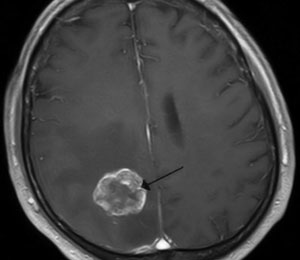

Trois ans après le diagnostic de mélanome métastasé, 94 % des patients développent des métastases cérébrales avec une médiane de survie moyenne d’environ 4 mois. Depuis la mise en évidence de l’intérêt de cibler les protéines mutées de la voie des MAP kinases, plusieurs molécules ont fait leur apparition sur le marché.

Après avoir démontré leurs intérêts en monothérapie sur la survie globale en comparaison aux cytotoxiques classiques (dacarbazine), des essais ont associé inhibiteurs de BRAF et de MEK pour contrer les résistances aux anti-BRAF seuls avec des résultats encourageants. Problème : le contrôle périphérique de la maladie est contrebalancé par l’incidence élevée des métastases cérébrales qui semblent échapper aux nouvelles thérapies ciblées, et pour cause : il a été montré que le vémurafénib et le dabrafénib passaient très peu la barrière hémato-encéphalique. Ils sont en effet efflués par la barrière hémato-encéphalique (BHE) par l’intermédiaire de protéines d’efflux, P-gp (Phosphate-glycoprotein) et bcrp1 (Breast cancer resistance protein).